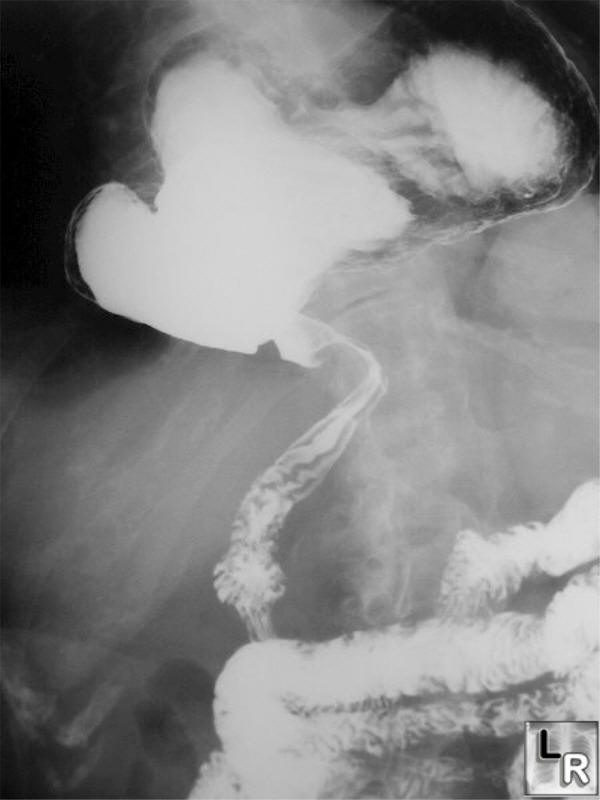

Gastric cardia radiology. Diagnostic centers of america dca is a leading diagnostic imaging facility offering a full array of imaging services in palm beach county florida. We have five state of the art radiology imaging centers in boca raton boynton beach delray beach and wellington florida. The gastric cardia is characterized on barium stud ies by three or four stellate folds that radiate to a central point at the gastro esophageal junction also known as the cardiac rosette fig 2 12. Variations and benign influences may closely resemble the more dangerous lesion.

Thick tortuous folds or lobulated filling defects in the cardia or fundus. Right gastroepiploic artery inferiorly and left gastroepiploic artery and short gastric arteries superiorly fundus of the stomach. Results of surgical treatment of carcinoma of the esophagus and gastric cardia. The collection of cases presented here comprises only that material which is rare in our experience or quite new to us.